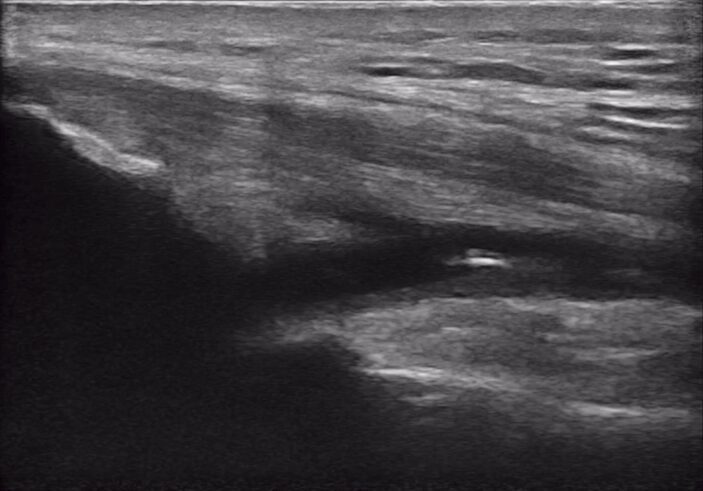

Precise Injections. Better Results.

Visualize targets in real time for precise nerve blocks and corticosteroid injections—reducing injectate volumes and boosting safety, confidence, and patient outcomes.

From pre-op to PACU, guide safe, accurate blocks and pain interventions without disrupting workflow or sterility.